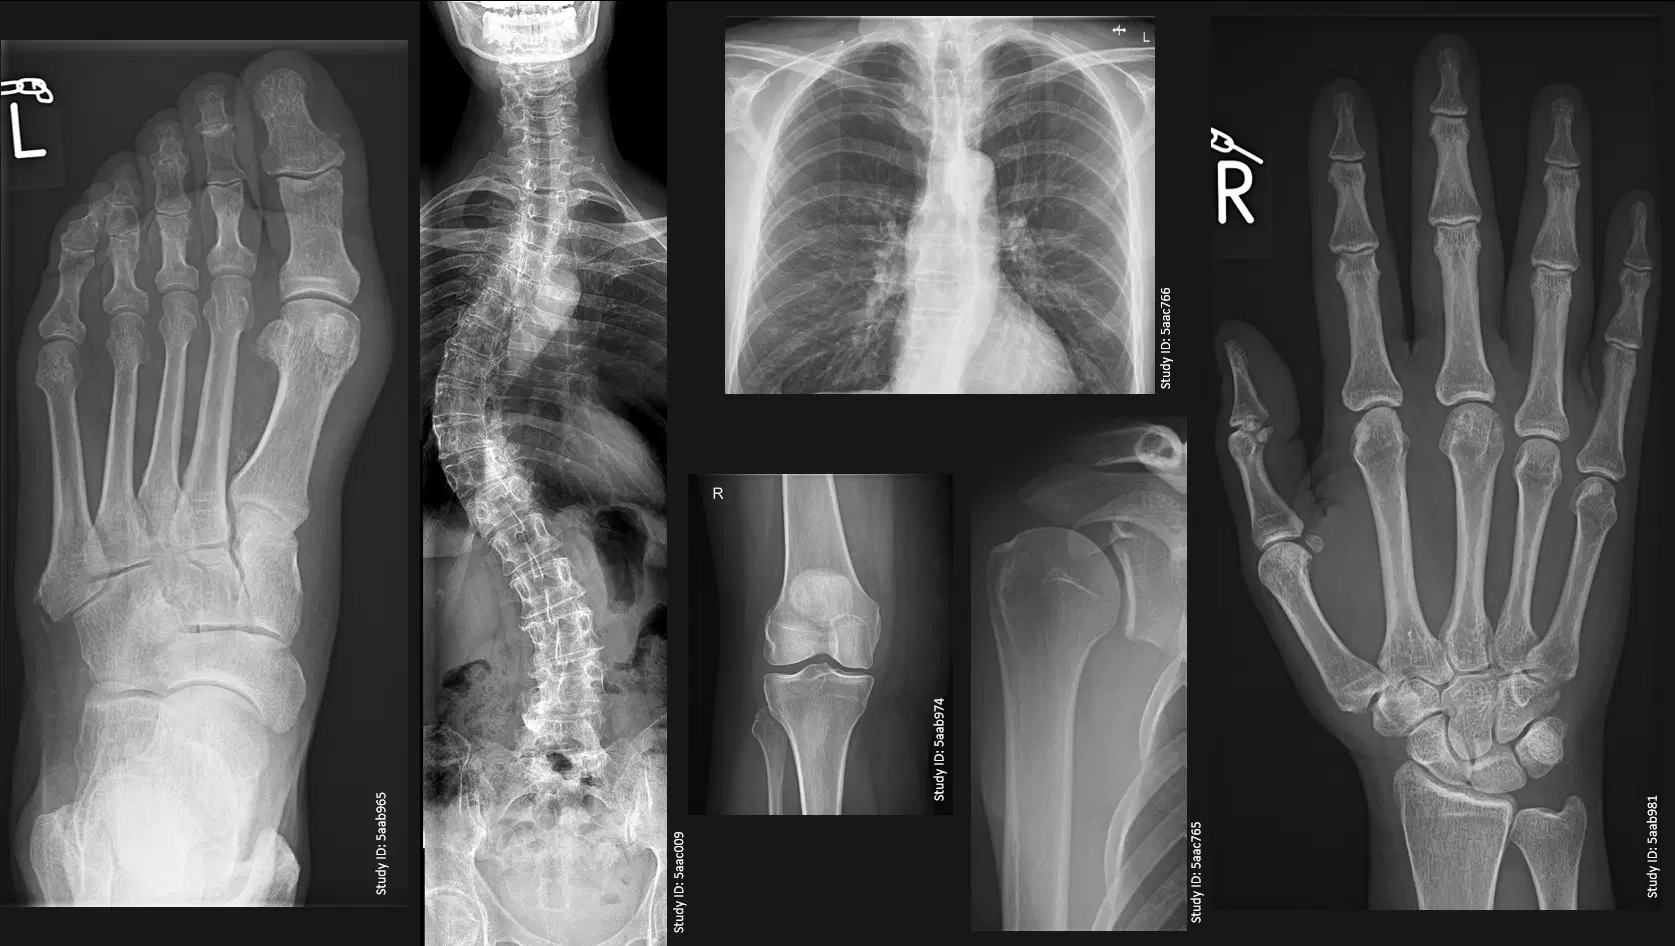

Centrul nostru este dotat cu SIEMENS Multix Impact VA20, un sistem radiologic digital avansat, echipat cu funcția Stitching radiologic digital. Aceasta permite obținerea, într-o singură imagine, a structurilor anatomice de mari dimensiuni, precum coloana vertebrală sau membrele întregi. Rezultatul: diagnostic precis pentru tulburări de statică vertebrală, instabilitate și inegalități ale membrelor inferioare.

Aparatul SIEMENS Multix Impact VA20 din dotarea centrului medical Medview are în dotare Stiching radiologic digital care permite vizualizarea într-o singură imagine a structurilor anatomice de mari dimensiuni cum sunt coloana vertebrală și membrele. Imaginile obtinute permit un diagnostic precis pentru o serie întreagă de afecțiuni precum tulburări de statică vertebrală, instabilitate vertebrală și inegalități ale membrelor inferioare.